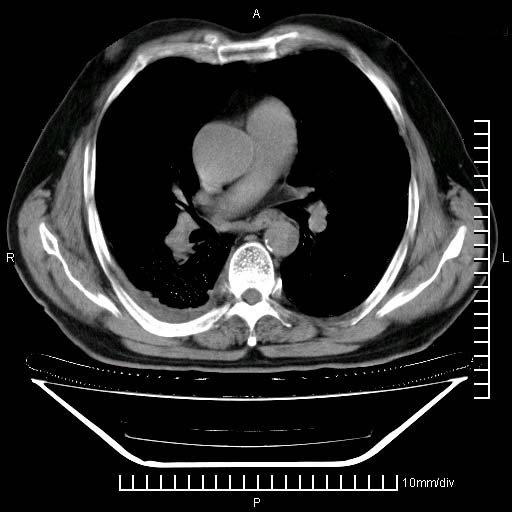

既往肺结核,近10几天,咳嗽,咳痰,右侧胸痛,疼痛较明显,右上肺斑块考虑结核灶胸膜粘连,增强,可惜动脉期没有定好,未见强化,可延迟4分后又见较明显强化,中心见低密度影,如果说结核是边缘强化,可这个灶强化的面积挺大的,让人很挠头。

动脉期